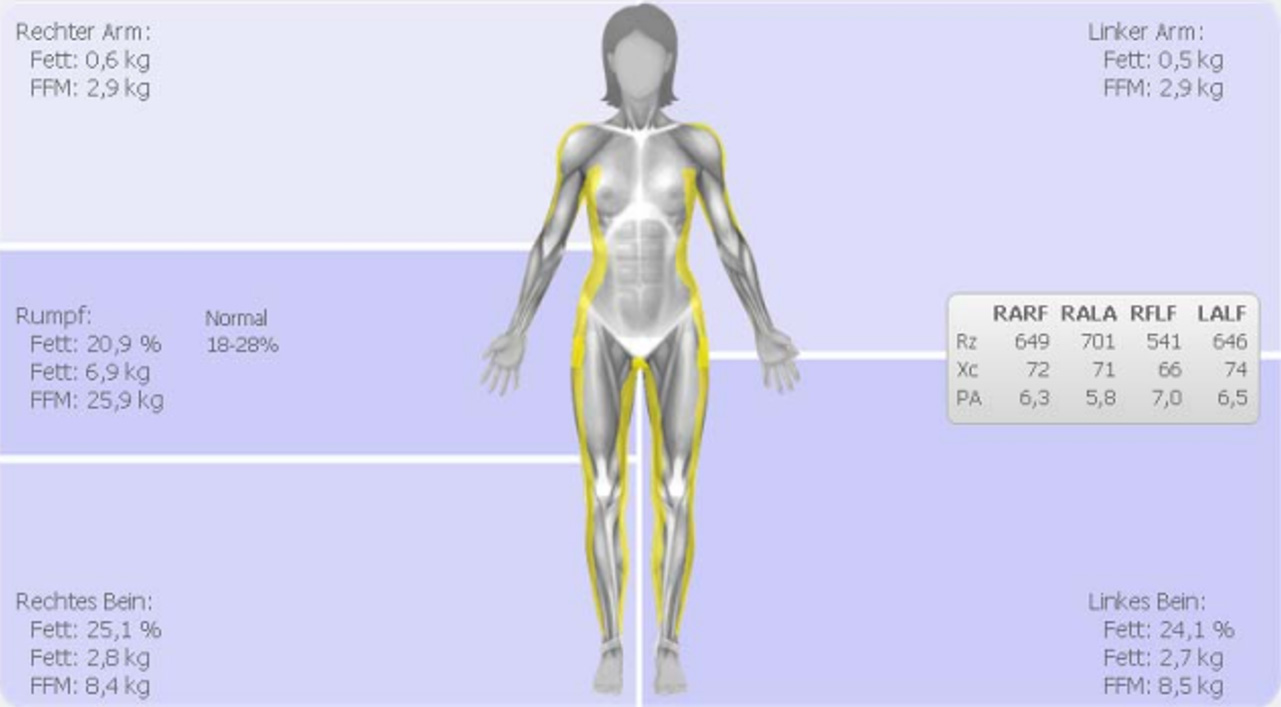

Beispiel einer Segment-Messung

Dargestellt werden die Segmente der beiden Extremitäten und der Rumpf. Die Fettmasse (FM) und die Fettfreie Masse (FFM) wurden gemessen.

Hier wird das Beispiel einer 10’000 Meter Läuferin gezeigt (59 Kg Körpergewicht). Anhand der Rohdaten Rz und Xc kann der unterschiedliche Trainingszustand der Körpersegmente erkannt werden.

Der Phasenwinkel der Beine ist mit 7.0 deutlich höher als derjenige der Arme mit 5.8, was bedeutet, dass die Beine mehr BCM enthalten.